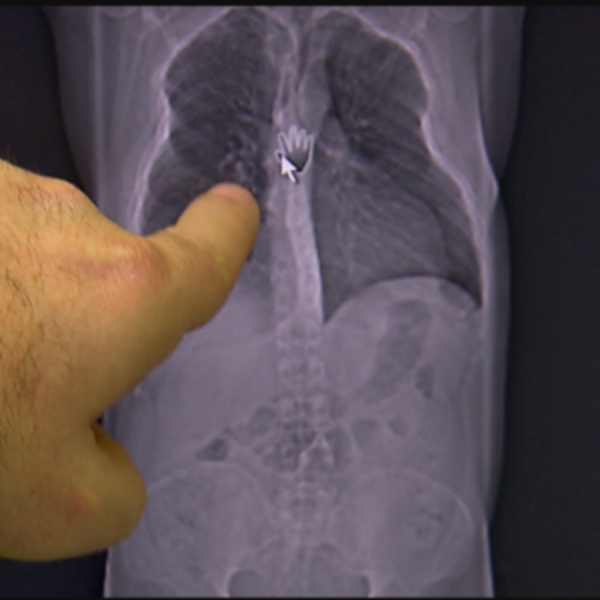

По данным Статистического управления Австрии, в 2019 году в Австрии умерло 83386 человек. Наиболее частыми причинами смерти были заболевания сердечно-сосудистой системы (38,6 процента) и рак (24,6 процента). Более половины смертей произошли после 80 лет.

В пожилом возрасте основной причиной являются сердечно-сосудистые заболевания, на втором месте - рак. Другими значительными причинами смерти были заболевания органов дыхания (6,3 процента), травмы и отравления (5,5 процента) и болезни органов пищеварения (3,6 процента).

Около 42 процентов всех смертей произошло в возрасте от 40 до 80 лет, причем рак является наиболее распространенной причиной: четыре из десяти смертей были вызваны карциномой, четверть - сердечно-сосудистыми заболеваниями и семь процентов - заболеваниями дыхательной системы.